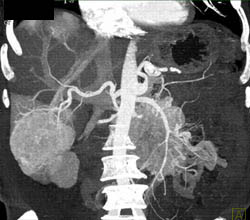

Islet Cell Tumor With Liver Metastases